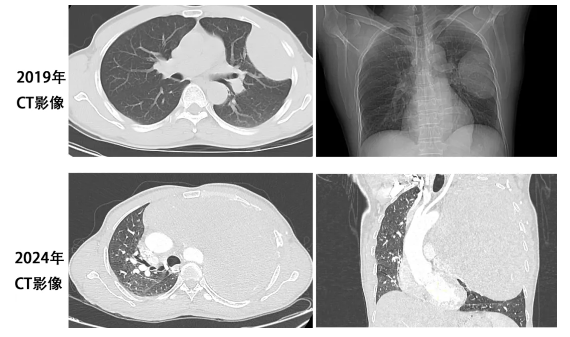

治疗前背景:患者黄某某,男性,56岁,2019年时因活动后气促行CT检查发现左侧胸腔内有一肿物影,大小约5cm*5cm*3cm,考虑良性肿瘤。当时未予重视,未行进一步检查及治疗。近年来,患者活动后气促逐渐加重,直到2024年5月再次就诊,行CT检查提示左侧胸腔肿物明显增大,约30cm*25cm*25cm,巨大的肿瘤几乎占据了整个左侧胸腔,并严重挤压纵隔、气管、心脏,导致以上重要器官出现明显移位。

在术前各种准备完善后,2024年9月18日顺利行手术切除,术中出血少,无需输血。肿瘤大小约25cm*20cm*23cm,重2.6KG。术中胀肺,使患者肺获得完全复张。术中、术后患者病情稳定,无需转重症监护病房,返回普通病房进一步治疗。第二天,患者顺利下床活动,复查胸片提示恢复好。